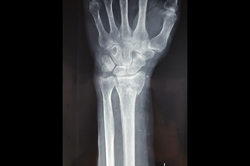

Lower Radius